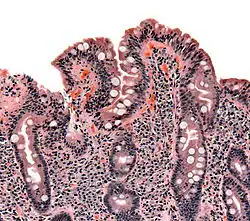

Selected image –

General images –